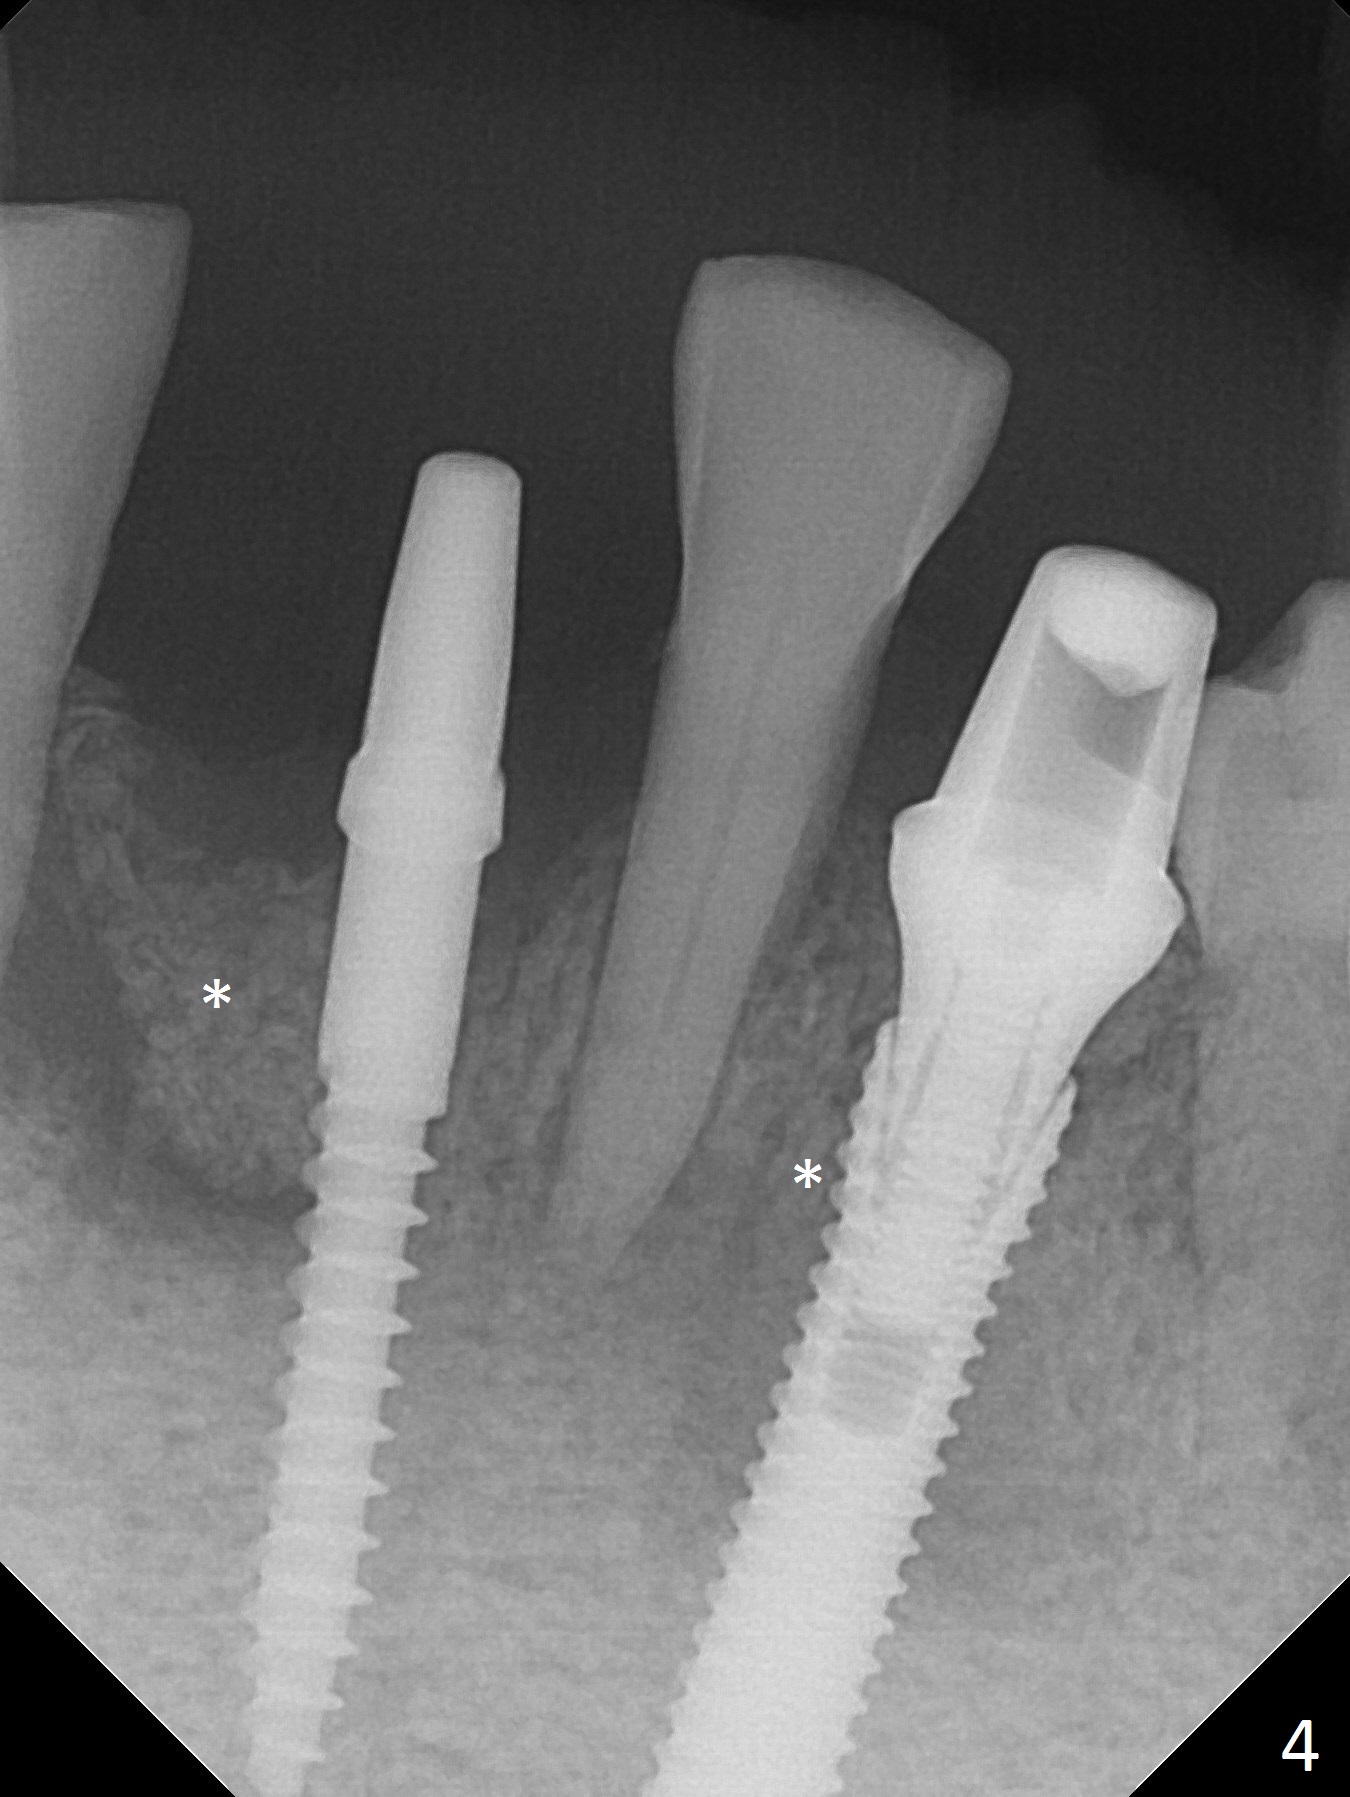

The depth of the osteotomy at #22 is 2-3 mm more than the expected implant length (Fig.2 with 2.7 mm drill in place). The implant at #22 (3.8x18 mm with insertion torque more than 50 Ncm) has clearance from the Incisive Canal and Mental Loop (Fig.3 red dashed line). Allograft with Osteogen is placed around the implants (Fig.4 *) in addition to Osteogen plug (cut in a thin layer) placed against the buccal wall of the socket at #22 (potential leakage). After suturing (Fig.5) and provisional cementation (Fig.6), periodontal dressing is applied (Fig.7). The implants seem to be ready for impression 4 months postop (Fig.8).